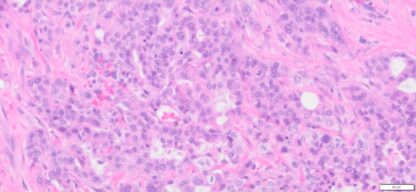

Description

| Tissue | Pathology Diagnosis | Gender/ Age (year) | %Tumor Area | Tumor Grade | TMN/Stage | IHC data |

| Pelvic mass | Human bile duct adenocarcinoma | Female/66 | 30% | II | T3N1M0 | MLH1,2,and6, PMS2 show intact nuclear expression |